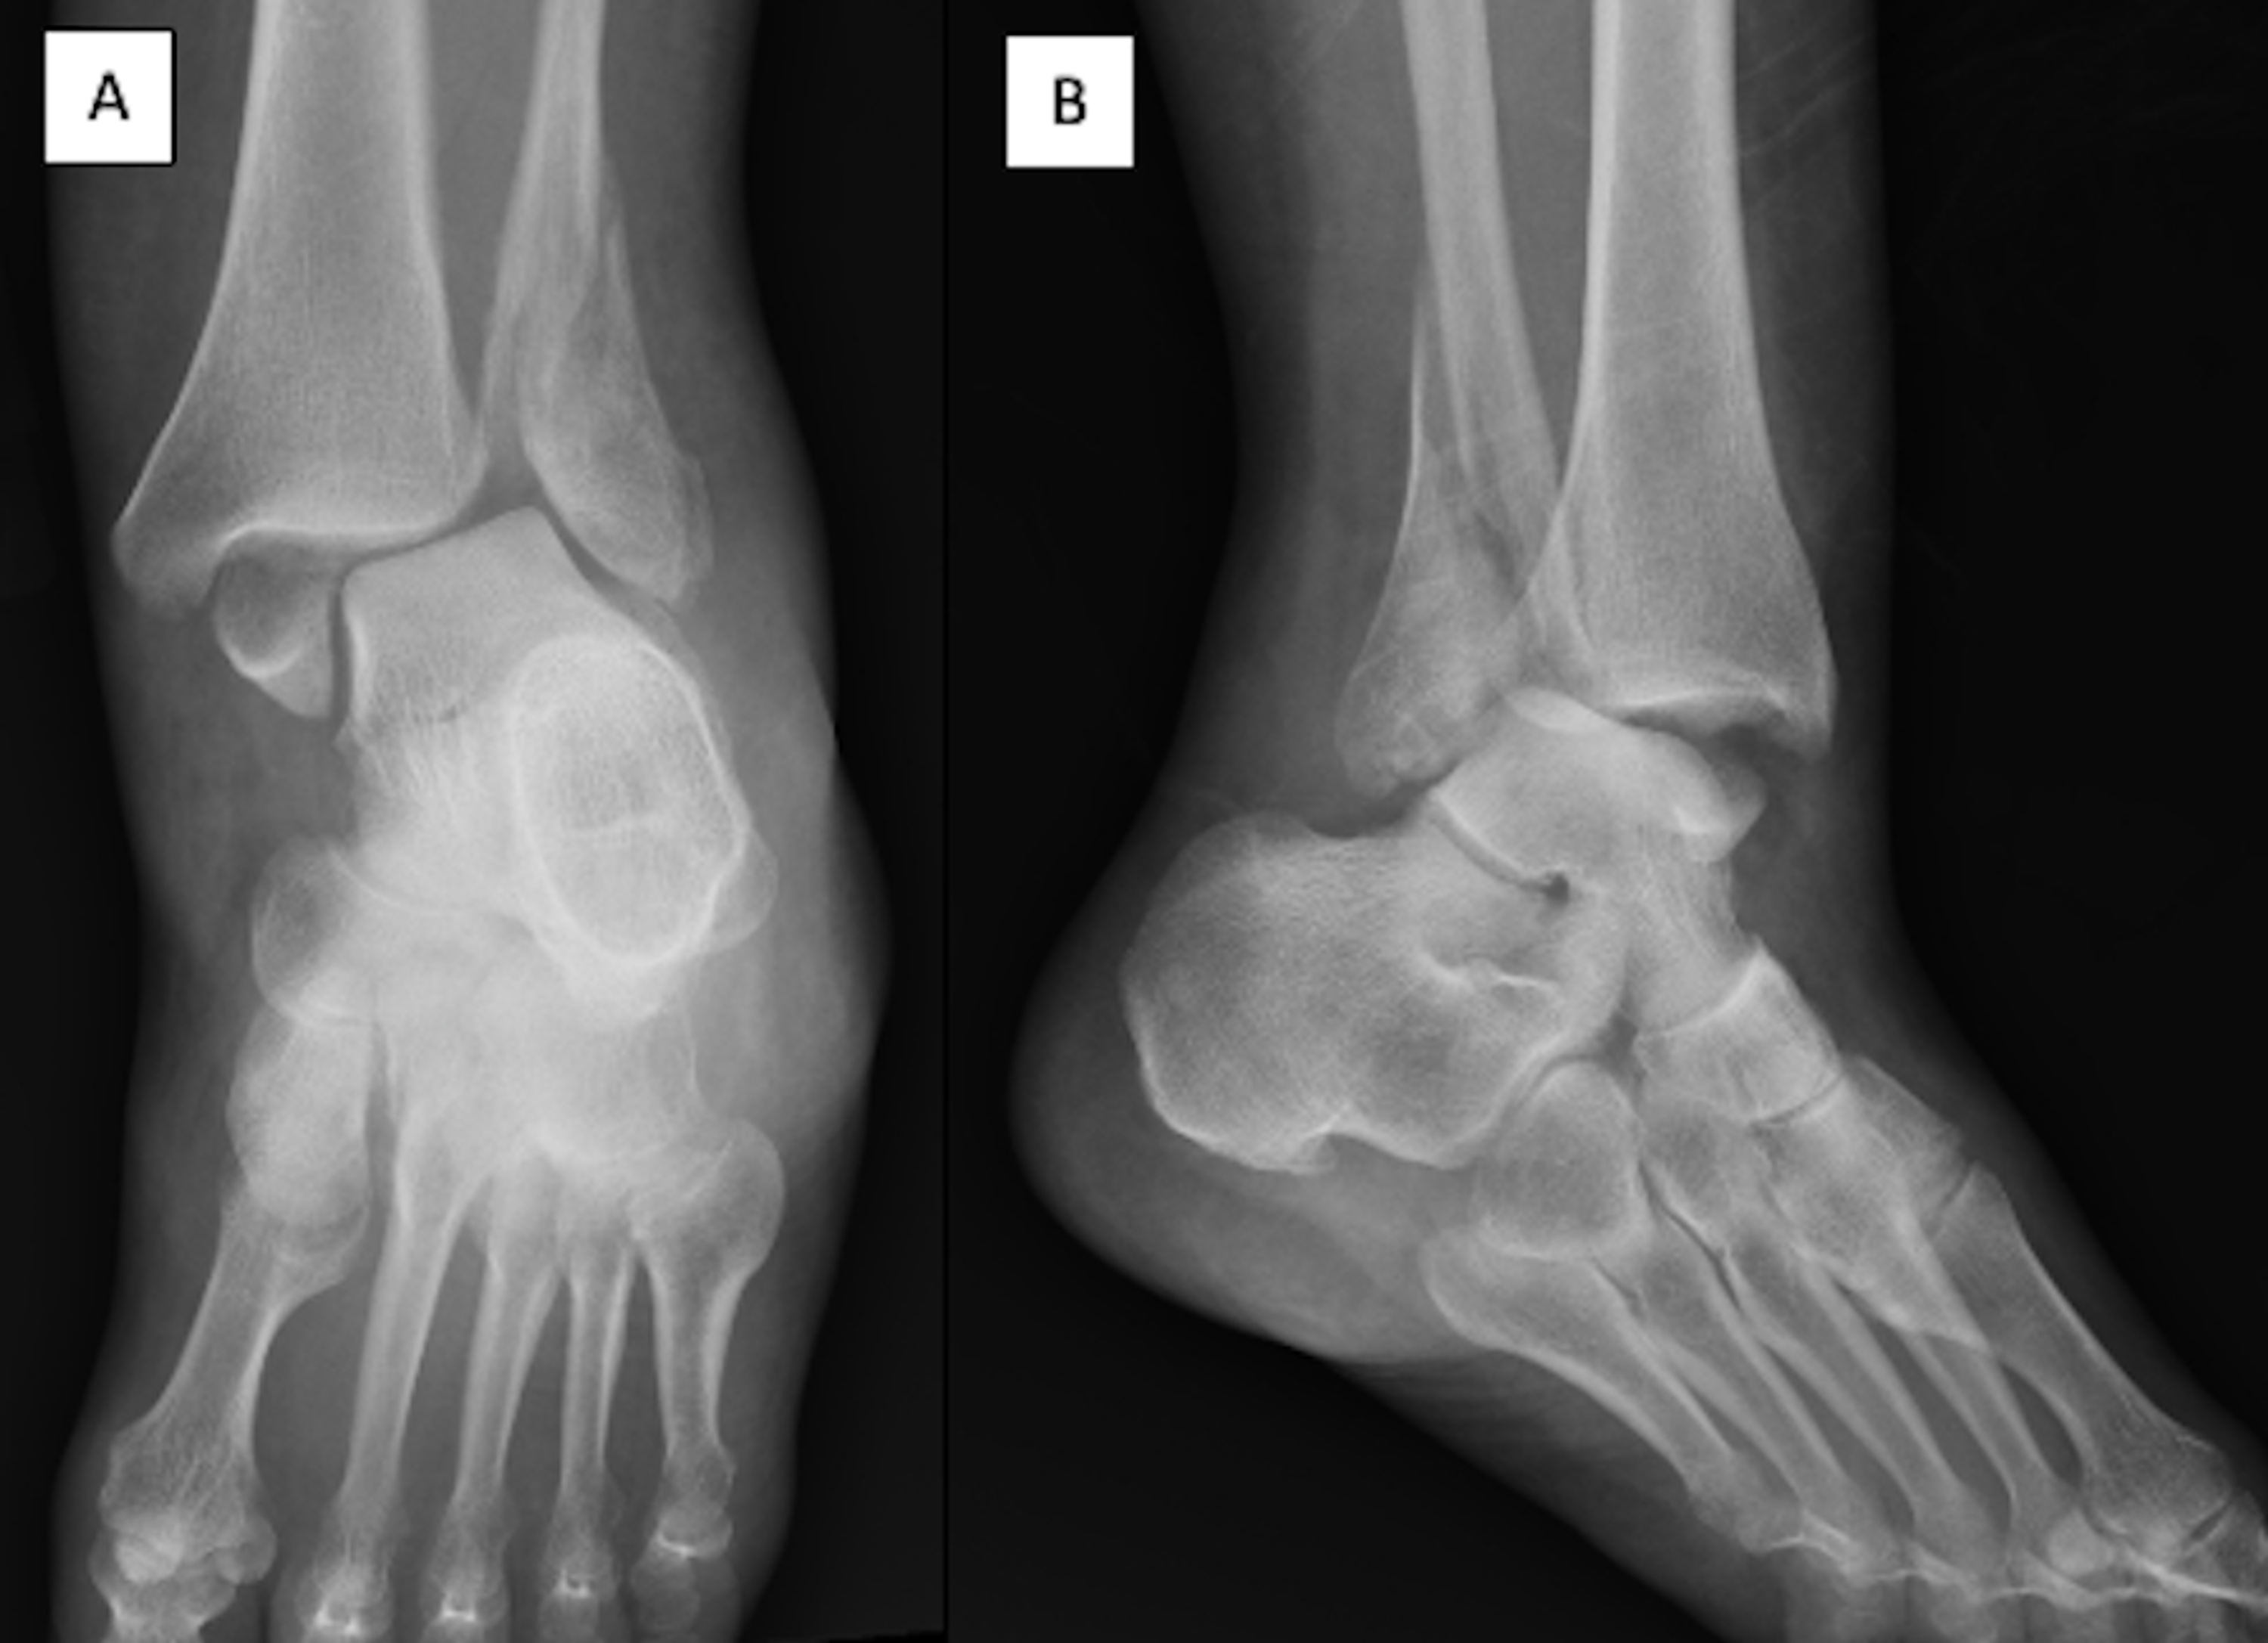

Fracture/Dislocation of the Ankle Trauma Case Studies CTisus CT

Fracture/Dislocation of the Ankle Trauma Case Studies CTisus CT All Fractures And Dislocations Are Reported Based On What This classification was based on dislocations occurring in all planes and consisted of total incongruity, partial incongruity, and divergent injuries. Study with quizlet and memorize flashcards containing terms like all fractures and dislocations are reported based on what?, use. Study with quizlet and memorize flashcards containing terms like all fractures and dislocations are reported based on what, the. All fractures. All Fractures And Dislocations Are Reported Based On What.